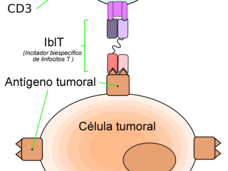

Blinatumomab extiende la supervivencia de pacientes con LLA avanzada

Pacientes tratados anteriormente para leucemia linfocítica aguda que recibieron blinatumomab, el cual incita al sistema inmunitario a destruir las células cancerosas, vivieron más y experimentaron menos efectos secundarios que los pacientes que recibieron quimioterapia convencional.